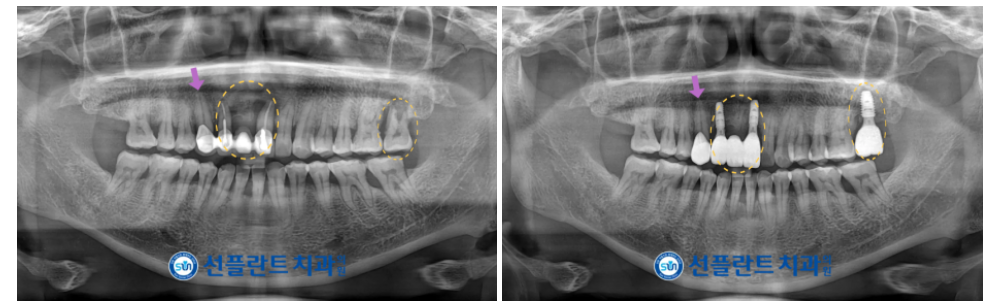

본원에서는

파노라마 사진과 3D CT 촬영을 통해

잔존 치조골의 양과 두께,

상악동 막과의 거리,

눈에 보이지 않는 해부학적 구조물 등을

면밀하게 파악하는 과정을 거쳤으며

.

이러한 결과를 토대로

명확한 위치와 방향으로

안정적인 임플란트 식립을 도와드렸습니다.

식립 후 충분한 시간이 지났을 때

임플란트와 잇몸뼈가 단단히 결합된 것을

안정적인 수치로 확인한 뒤

위턱 오른쪽 송곳니(#13) 보철물을 포함하여

최종 보철물 제작을 위한

인상채득을 진행하였는데요.

최종 보철물은

자연치아와 강도가 유사하고

심미적인 지르코니아로

마무리해 드렸습니다.

모든 치료가 마무리된

구강 내 사진과

파노라마 사진인데요.